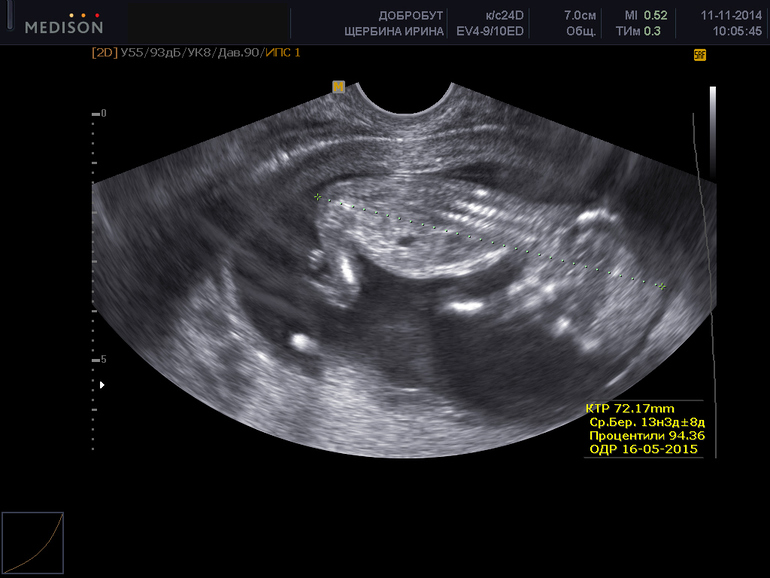

Предполагаемая дата родов 23 мая